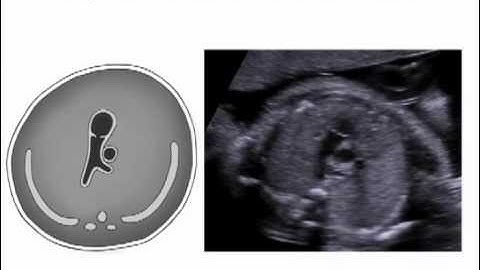

Part 4 - Right ventricular outflow color and PW Doppler